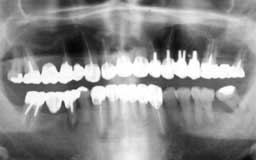

Yさん 初診時 54歳 女性

残存歯総数26本ですが、大量の歯石と上顎臼歯部の歯槽骨破壊が不気味です

Yさん 21年後 75歳

初診時以来歯を失うことなく順調に経過しています